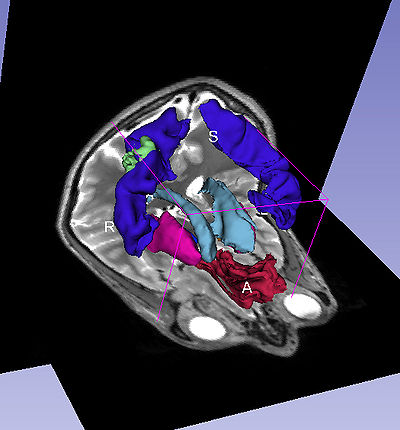

The Query Results panel shows the result of a query, consisting of all the associated predicates and parts for the query. The Figure User Page GUI shows the result of a simple query "limbic system".Additionally, the interface also shows a Comment that contains any relevant textual information about the query obtained from the ontology. The user can refine a search by selecting from the query result. Optionally, the user can also select by clicking on any selection from the Query History or Favorite Queries panel to redo search and visualization. The interface supports the multiple selections to form complex queries. The visualization resulting by searching with the query "Limbic system" is shown below.

A complex query contains two or more simple or specialized queries. A complex query is typically specified by using a "+". Note that the "+" does not signify an ANDing of the search terms. Instead each string separated by the "+" is searched as an individual query in the ontology. The result of using a complex query is shown below. The Application interface shows the results for all the terms that are matched in the ontology (i.e. the motor system and straight gyrus.) Unmatched terms such as the user added models (e.g. mass) are only displayed. The figure shows an example of a complex query comprised of simple queries.

Specialized queries can be combined with other simple or specialized queries to form complex queries (e.g. "motor system + straight gyrus;synonym"). An example of a complex query using specialized and simple query terms is shown below.